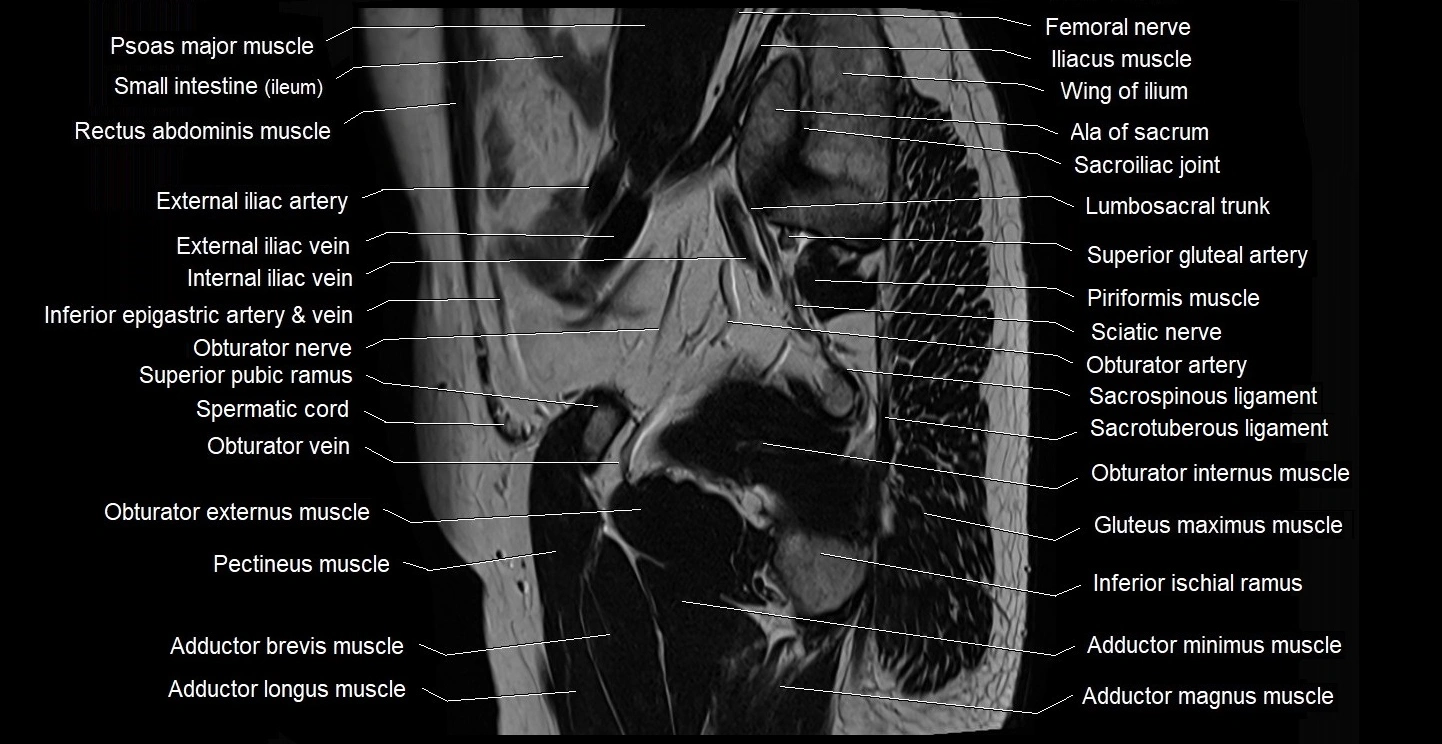

- Adductor brevis muscle

- Adductor longus muscle

- Adductor magnus muscle

- Adductor minimus muscle

- External iliac artery

- External iliac vein

- Gluteus maximus muscle

- Lumbosacral trunk

- Obturator externus muscle

- Obturator internus muscle

- Pectineus muscle

- Piriformis muscle

- Psoas major muscle

- Sacral plexus

- Sacrospinous ligament

- Sacrotuberous ligament

- Sciatic nerve

- Spermatic cord

- Superior gluteal artery

- Superior pubic ramus